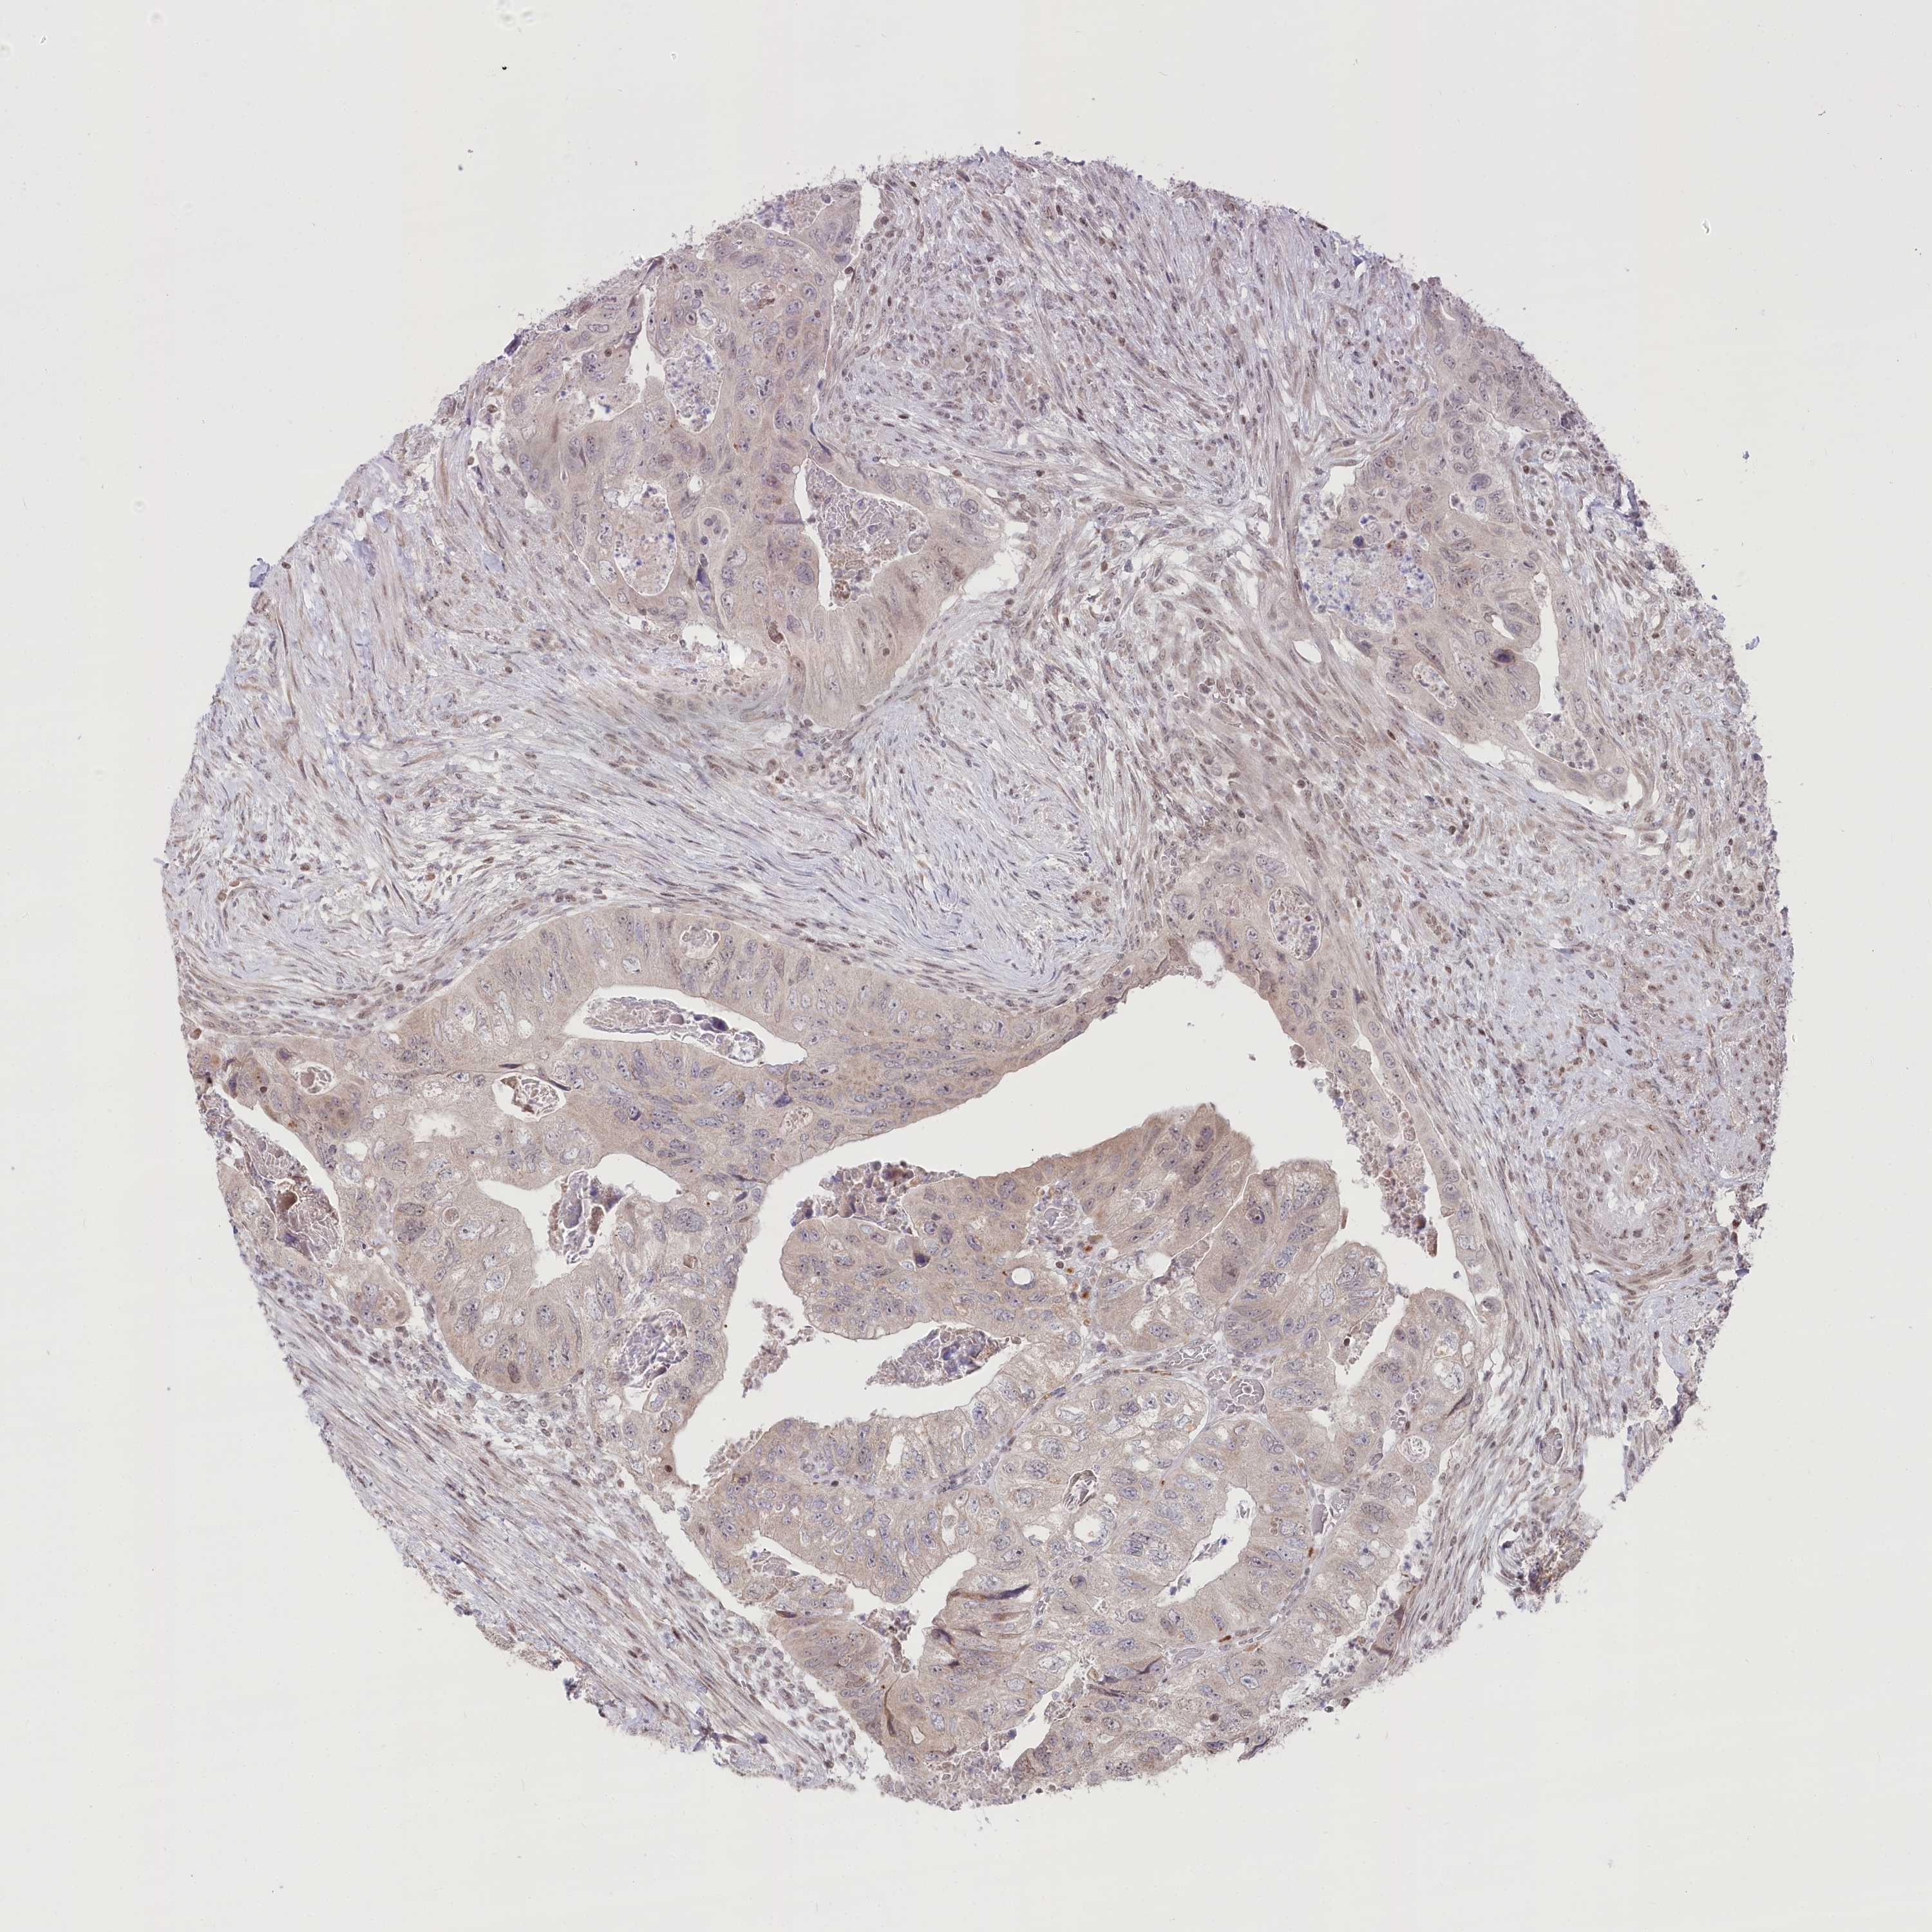

CANCER COLORECTAL CANCER Show tissue menu

Colorectal cancer

Human cancer

Colon adenocarcinoma